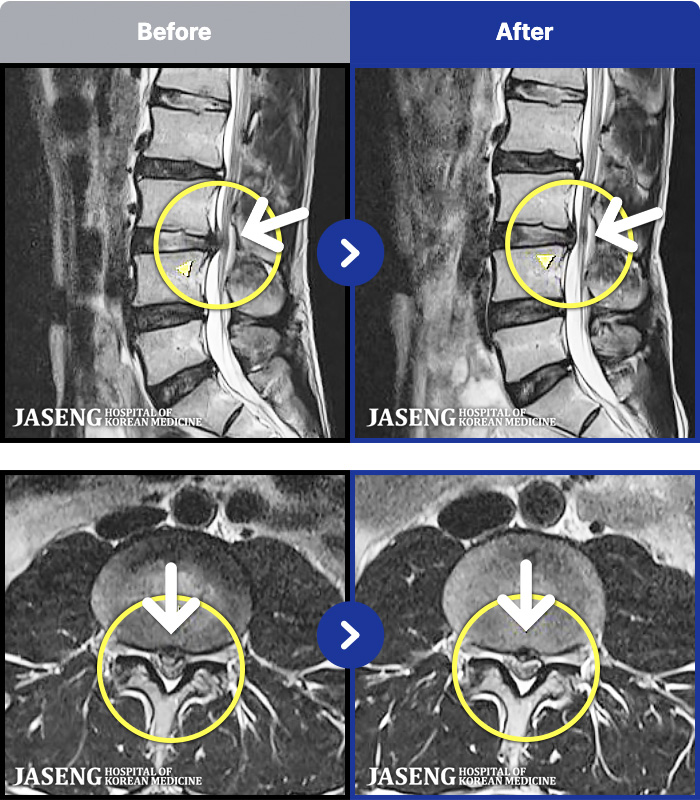

1,298 MRI ũ ʸ Ȯϼ.

[] 23.11.11~25.06.04